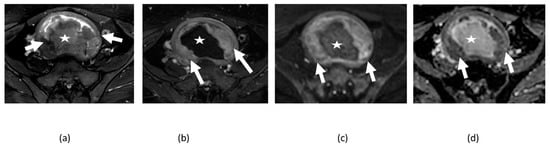

5. Pitfalls of DWI

5.1. T2 Shine-Through Effect

5.2. T2 Blackout Effect

5.3. Diagnostic Pitfalls